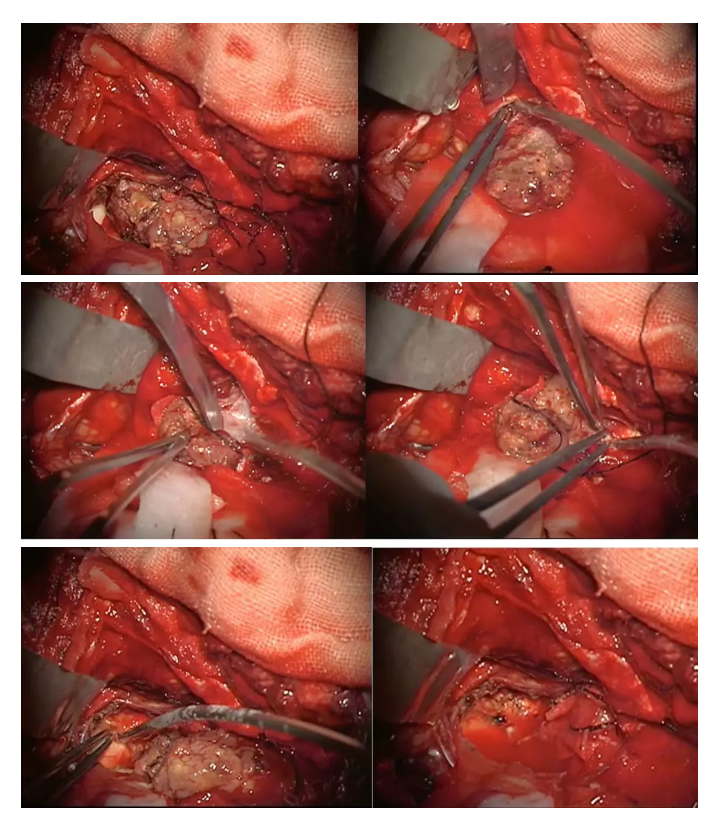

手术切口设计

显微镜下整块、全切肿瘤,脑干背侧显示清晰。